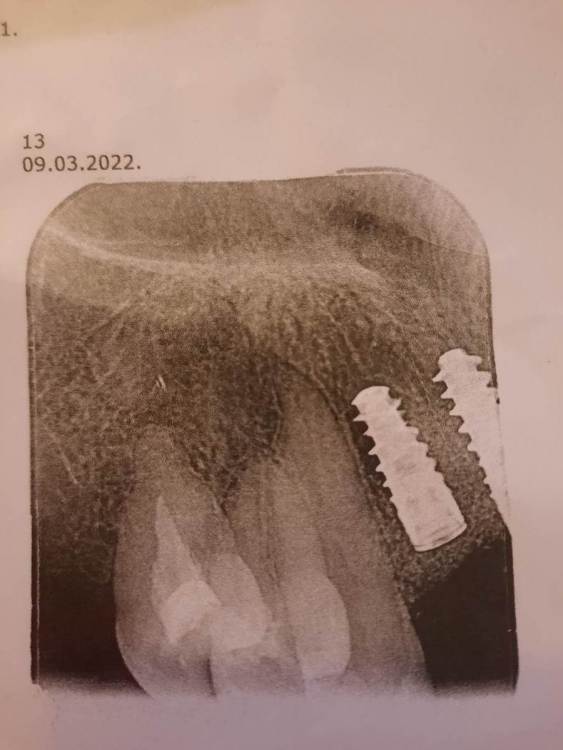

IrinaT Опубликовано 20 марта, 2022 Автор Поделиться Опубликовано 20 марта, 2022 Продолжение. По пути заболел хронически больной зуб 1.6. Эндодонт (с микроскопом) сказала, что перелечивание такого зуба (там в канале остатки инструментов) даже с микроскопом не будет давать гарантию, лучше удалить и потом тоже имплантат. Удалила 1.6 в середине февраля, то есть, более месяц назад, сложное удаление, с распиливанием, отеком итд. И вдруг заболел зуб 1.3, который рядом c имплантатом. Опять к эндодонту, сказали, что 1.3 не нуждается в каком либо лечении. Воспаления там нет, живой зуб. Пошла имплантологу, он сказал, что то, что я назвала пульсацией, есть поведение сосудов, которые были травмированы во время подсадки кости и имплантата. То есть - сосуды разширяются во время физической нагрузки, если пить горячее или стресс. И появляется как бы пульсация на некоторое непродолжительное время. Сделали КТ (с собой не дают КТ) - сказали в имплантатах воспаления нет. Но потребуется пересадка десны, то есть пластика десны, но это потом. Нигде в интернете насчет сосудов не могу ничего найти. После имплантации уже 4 месяца, а так сказали ждать 6 месяцов. По этому рентгеновскому снимку, который сделал эндодонт на жалобы на зуб 1.3, может можно сказать - есть ли воспаление в импланте? У меня температуры нет, ничего другое (голова, нос) не болит. Но беспокоит зуб 1.3. Боюсь остеомиелита. Это отголосок от удаленной шестерки? Или от импланта? Что делать? Искать еще консультацию и опять делать КТ? Ссылка на комментарий

Irouil Опубликовано 20 марта, 2022 Поделиться Опубликовано 20 марта, 2022 Явных проблем на снимке не видно, но он и не особо информативен. Попробуйте получить сделанное КТ, возможно запись снимка на носитель стоит дополнительных денег в клинике Ссылка на комментарий

Pavel-Pskov Опубликовано 21 марта, 2022 Поделиться Опубликовано 21 марта, 2022 Вроде всё норм. Ссылка на комментарий